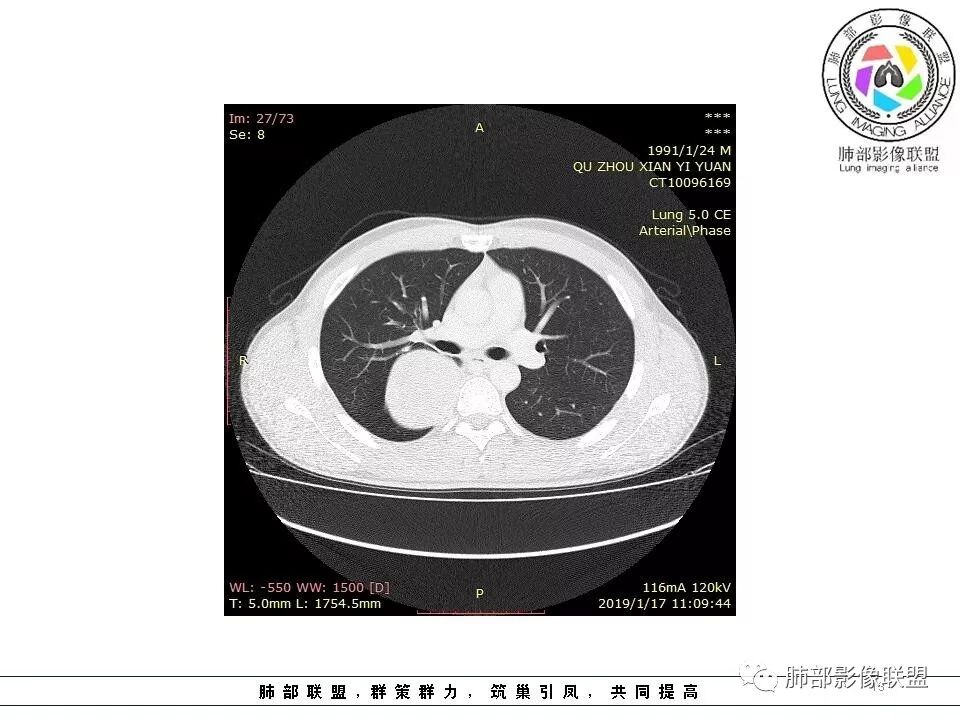

后纵隔脊柱旁占位性病变,疾病谱有神经鞘瘤,sft,节细胞瘤,髓外造血。此例有胸膜尾征,蛇纹征 ,延迟强化。考虑胸膜孤立性纤维瘤。看到有供血动脉,但不知道是哪里的血管。

后纵隔类圆形新生物,边缘光滑,胸膜尾征明显,贴近脊柱,蛇纹,血供丰富,考虑后纵隔软组织肿瘤,具体类型看不出来,鉴别神经鞘瘤。

右侧后纵隔脊柱旁占位,边缘光滑清晰,内侧肺组织受压,外侧可见胸膜尾征,增强持续强化,并可见蛇纹血管征。考虑SFT

右肺占位,跨越上叶后段、下叶背,边缘光滑,瘤肺界面清,见肺压缩缘(线样不张`强化),见胸膜尾征,胸膜下脂肪未见明显增厚,肋骨丶脊柱未见侵袭及受压,渐进性丶地图样强化,冠状位似见体循环供血

诊断:SFT(来源壁层胸膜?一般小于20%)

边缘光滑,宽基底与胸壁相连,跨叶裂,叶裂稍前推,血管、支气管前移。

浅分叶

外上侧少量胸水

肋间动脉供血,强化尚均匀,逐步强化